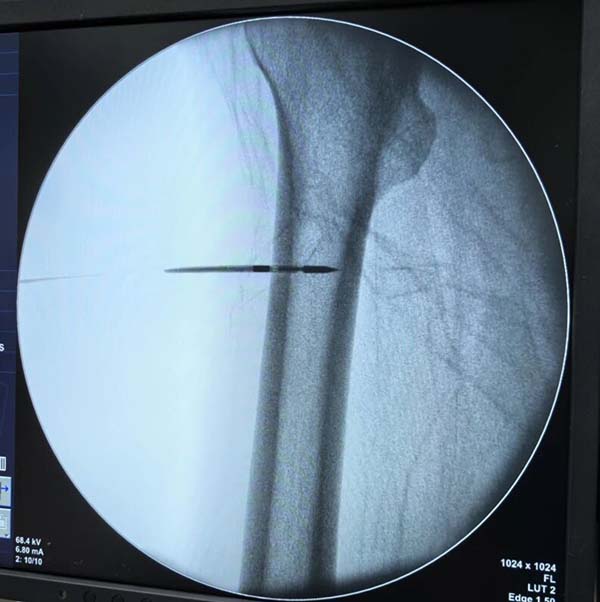

经多学科会诊(MDT),团队制定“微波消融+骨水泥填充”微创个性化方案。术中在C型臂精准引导下,直径仅2毫米的消融针直达肿瘤核心,通过高频微波产生100℃以上高温,实现肿瘤组织瞬间凝固性坏死,同时注入骨水泥强化骨骼支撑。术后复查X线显示消融范围覆盖病灶,骨水泥填充稳定。